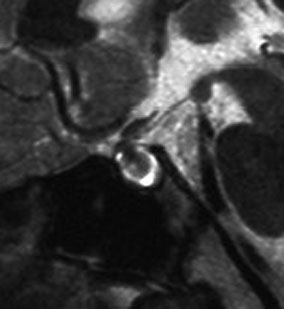

尿崩症で発症した小さな腫瘍

尿崩症で発症した9歳男児にみられたxanthogranuloma of the sellar resion。左はT1強調画像で高信号,右はT2強調画像で低信号であり,肉芽腫の特徴がみられます。のう胞部分はT2強調画像で,高信号になります(右図)。このような小さな頭蓋咽頭腫やラトケのう胞が尿崩症を呈することはまれですが,黄色肉芽腫の場合は小さくても症候性となることが多いです。神経下垂体組織が炎症性に破壊されるからと考えられます。